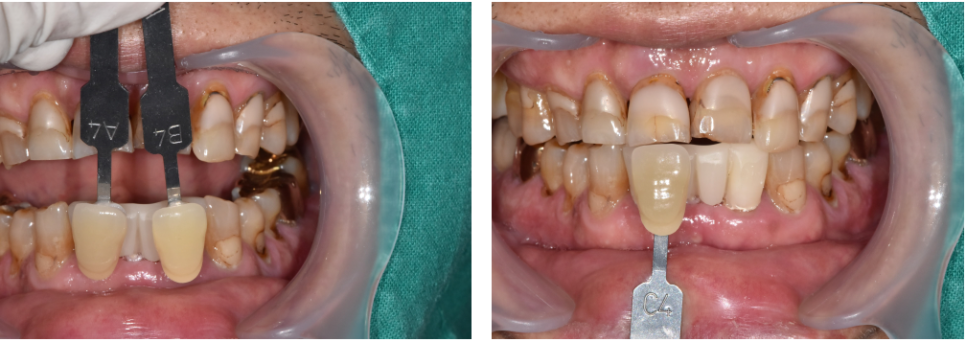

앞니쪽이기 때문에 최대한 티 안나고 자연스럽게 제작해드리기 위해

저희 바르디 치과에서는 치아 사진을 찍어 보철물 제작을 의뢰 하고 있습니다.

(치아색상표를 이용하여 최대한 주변 치아색에 맞추어 자연스럽게 제작합니다 ^^)